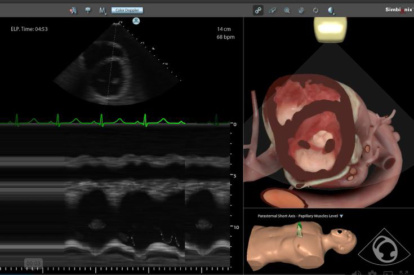

Ultrasound Mentor accelerates the development of basic to advanced technical and cognitive skills, by providing not only the probe manipulation training, but also a didactic environment enabling structured, self-guided learning including step-by-step instructions and educational aids such as 3D anatomical map and probe positioning assistant, all backed up with our progress monitoring tool MentorLearn.

- Advanced diagnostic tools, including Color Doppler, CW, PW, M-mode, and measurements

Bedside Echocardiography Module

Advanced Echo Module

TEE Module

TEE Emergency Module